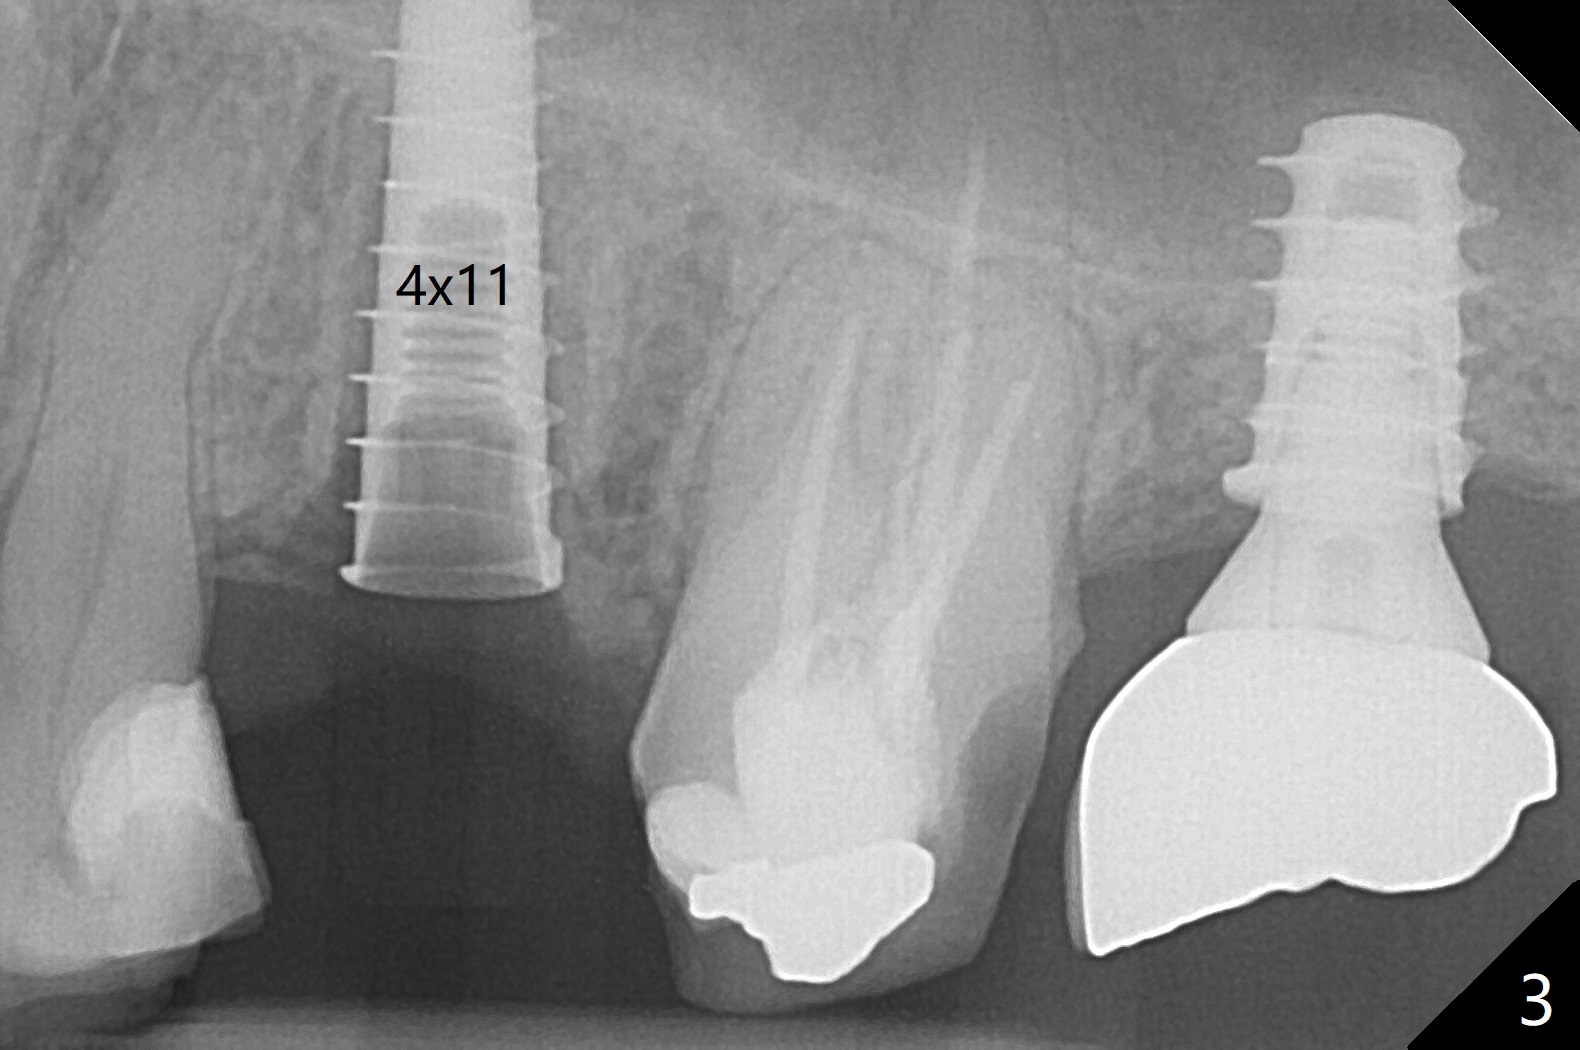

The patient with the anterior cross bite at the left lateral and canine and incipient Class V caries returns to clinic for #13 residual root extraction (Fig.1,2). There is no quality root structure (Fig.2) or space (Fig.3) for socket sheath. Two amalgam carriers of Vanilla is inserted and pushed by the 4x11 mm dummy implant for sinus lift (Fig.4 *). When the same sized final implant (4x11 mm) is placed, a 5.5 mm bone profile drill is used to trim the proximal crests (Fig.5 * sticky bone packed in the buccal and palatal gaps). In fact the implant turns when a 4.5x4(3) mm pair abutment is tightened. The implant is backed up; with a healing screw, sticky bone is placed (Fig.6 *) and then covered with a piece of PRF and a part of GEM cap. The wound is sutured with 4-0 PGA; periodontal dressing is applied. The implant is somewhat over-seated without the bone graft covering the apical end of the implant (Fig.7, as compared to Fig.4). A 4.5 mm implant should be placed. The GEM Cap appears to be absent 9 days postop, while the periodontal dressing dislodged in 1 week (Fig.8). It appears that the existing abutment at #15 is incompletely seated (Fig.3, 5.5x4(2) mm). After use of 5.5 and 6.0 mm bone profile drills, a 5x4(3) mm abutment is placed with 35 Ncm torque. In fact the bone graft coronal to the implant remains (Fig.9 *) in spite of apparent loss of the overlying PRF and GEM cap (Fig.8). After use of a 4.6 mm profile drill, a 5.5x3 mm healing abutment is placed 4.5 months postop (Fig.10). Without a provisional at #13 for ~ 4 months, there is a gap between crowns at #14 and 15 (not shown due to angulation). Impression is taken for #13 crown fabrication 5.5 months postop and for #15 crown repair (addition of porcelain for the mesial contact, Fig.11). It appears critical for a provisional to maintain the position of the neighboring tooth.